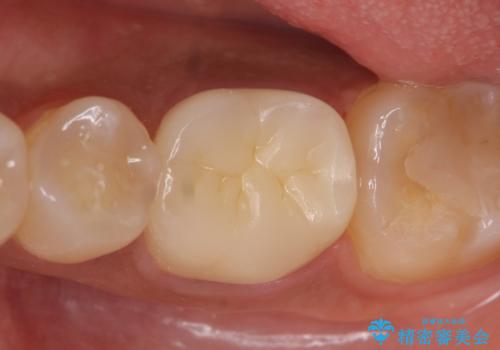

その後症状の緩解を確認後、オールセラミッククラウンによる補綴を行いました。

今回用いたオールセラミッククラウンはジルコニアフレームという白い素材の上にセラミックを盛っているため、審美性が非常に高いのが特徴です。

また、ジルコニアは人工ダイヤモンドの材料にも使われているほど高い強度を持っており、そのためオールセラミッククラウンは審美性だけでなく、奥歯やブリッジの補綴も可能とするクラウンです。